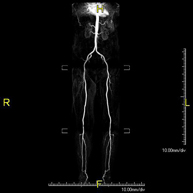

Prova diagnòstica no invasiva que consisteix en l'estudi vascular del sector aorto-ilíac i dels vasos arterials de les dues extremitats inferiors, am l'obtenció d'imatges d'alta definició anatòmica mitjançant l'ús d'un camp electromagnètic i ones de ràdio (amb un emissor i un receptor). És indispensable l'ús de contrast paramagnètic (Gadolini). No obstant, no utilitza radiació ionitzant. La qualitat de les imatges permet realitzar reconstruccions en 2D i 3D. Està especialment indicat en aquells pacients en els que hi ha sospita de malaltia vascular a les dues extremitats, en pacients amb malaltia vascular de les dues extremitats com a mapa vascular abans del tractament (percutani o quirúrgic), com a mapa vascular prequirúrgic en pacients amb lesions òssies o musculars que requereixin cirurgia, etc. - Angio-RM d'Artèries renals

Prova diagnòstica no invasiva que consisteix en l'estudi de l'artèria aorta abdominal per obtenir imatges d'alta definició anatòmica mitjançant l'ús d'un camp electromagnètic i ones de ràdio (amb un emissor i un receptor). És indispensable l'ús de contrast intravenós paramagnètic (Gadolini). No obstant, no utilitza radiació ionitzant. La qualitat de les imatges permet realitzar reconstruccions en 2D i 3D. Està especialment indicada en pacients amb sospita de malaltia vascular de les dues extremitats, en pacients amb malaltia vascular de les dues extremitats com a mapa vascular abans del tractament (percutani o quirúrgic), com a mapa vascular prequirúrgic en pacients amb lesions òssies o musculars que requereixin cirurgia, etc. - Angio-RM Lesión partes blandas